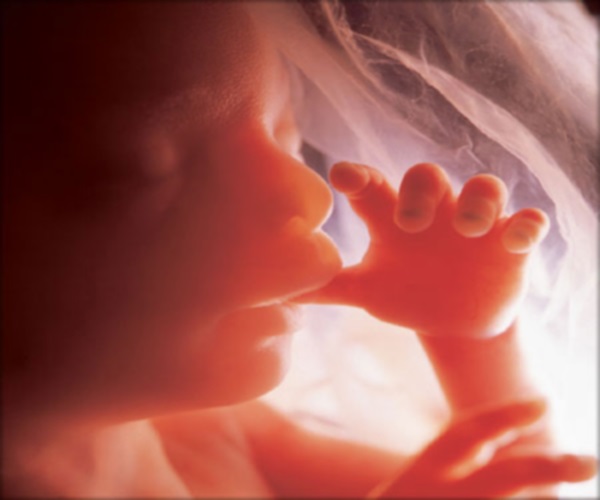

Thai nhi 14 tuần tuổi đã biết mút tay

- Thai nhi tuần thứ 14 có thể mở miệng, thở và nuốt nước ối.

- Thai nhi 14 tuần tuổi có thể di chuyển và đạp nhẹ vào thành bụng của mẹ. Tuy nhiên, hầu hết các hành động này mẹ sẽ vẫn chưa cảm nhận được.

- Bé biết mút tay, nắm lấy dây rốn và tự buông ra khi lượng máu lưu thông bị hạn chế.

- Bé có thể cử động các cơ mặt như: nhăn mày, lo lắng, cau có, giận giữ,…